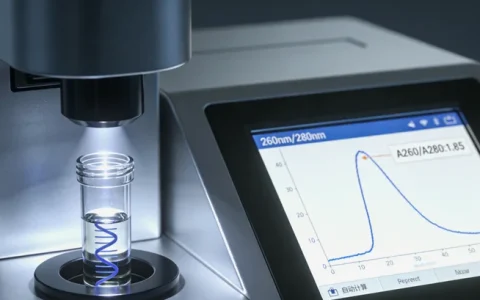

目前,标准的做法是用手术切除或穿刺活检取得的肿瘤组织样本进行检测,这是“金标准”。有时也会同时抽取外周血,用来区分突变是肿瘤特有的(体细胞突变)还是天生就有的(胚系突变)。对于孩子来说,取样过程和治疗中的活检或手术同步完成,不会增加额外的创伤。

费用方面,一次基于NGS(下一代测序)技术的检测,市场价通常在几千到一万多元不等。它确实是一笔开销,但请这样想:它可能直接避免无效或过度治疗,找到救命的靶向药,从长远看,可能是更经济、更有效的选择。有些地区医保或慈善项目能覆盖部分费用,可以具体咨询。